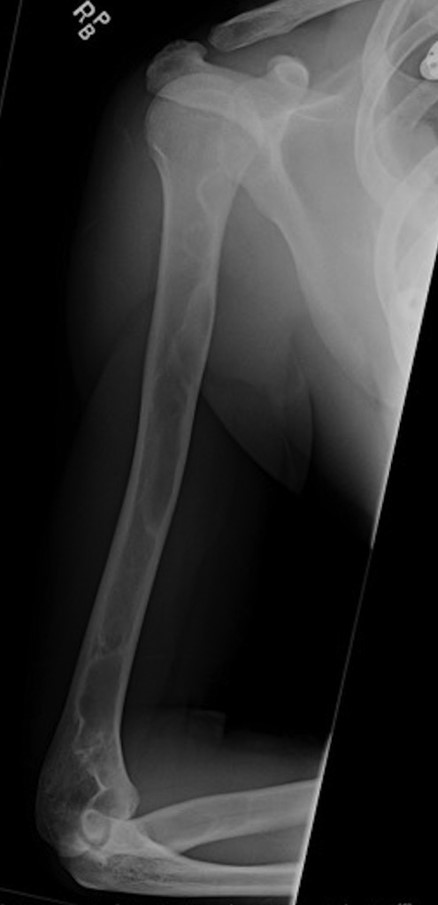

Chest x-ray revealed a destructive lesion in the posterolateral right fourth rib with associated soft tissue component consistent with FD. A CT of the chest revealed cortical thickening and ground-glass appearance of the right fourth rib (Fig. 3). A lytic lesion was noticed in the posterolateral fourth rib with a soft tissue component and cortical thinning adjacent to the area of FD appeared consistent with ABC. MRI of the chest revealed a 7 cm × 3 cm complicated cystic lesion within the right fourth rib with fluid levels consistent with ABC (Fig. 4). The skull lesion represented the most accessible site for biopsy and possible excision. For completeness, a bone scan was performed to evaluate other areas of involvement and remarkably the scan revealed increased uptake in the right frontal region, right fourth rib and in the right upper extremity. X-rays of the right upper extremity revealed non-expansile ground-glass process within the humerus and proximal one-third of the radius consistent with a history of FD with ABC formation (Fig. 5). The patient denied right extremity pain and was not tender to palpation along upper extremity.